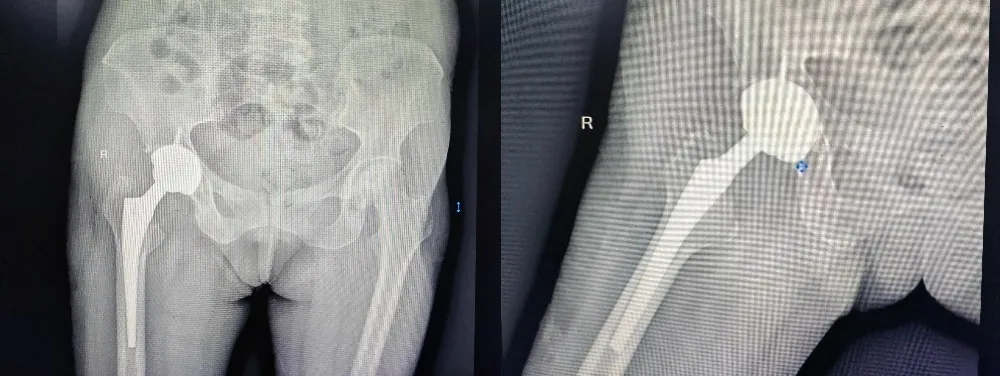

手术当日,真正的挑战呈现在主刀团队眼前。当打开患者的髋关节后,情况比影像所见更为复杂。在长期激素影响下,该患者的骨骼质量极差,如同“朽木”;坏死的股骨头严重塌陷、变形,与髋臼粘连致密,正常的解剖结构已面目全非。

这要求手术团队不仅要有高超的常规关节置换技术,更需具备处理极端复杂骨缺损和畸形的经验与应变能力。主刀主任医师赵军凭借丰富的经验和术前精细规划,如同一位精巧的“建筑师”首先精细松解,要小心剥离粘连组织,保护重要的神经血管。接下来精准截骨,在变形的股骨颈上找到最佳截骨平面。最后重塑“地基”,患者髋臼侧存在巨大骨缺损,团队采用自体股骨头骨块进行结构性植骨,重建了髋臼的正常形态和包容性,为人工髋臼杯的稳定放置创造了条件。

手术全程在麻醉团队的严密监护下平稳进行,出血量控制良好。当试模复位后,关节活动度良好且稳定,标志着手术取得了关键成功。